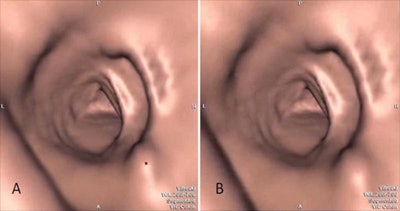

The investigators recorded 15 endoluminal CTC examinations, generating two videos each -- one with and one without CAD marks. Each case had a single polyp. A total of 42 readers, including 17 experienced and 25 inexperienced, interpreted the videos during a visual search, and their pupil eye movement was recorded using eye-tracking technology (Tobii X50 or X120 eye tracker, Tobii Technology) that was placed beneath their viewing screens.

"When viewing in an endoluminal flythrough mode, there is a 'window of opportunity' during which you have time to see a polyp because when it's moved off the screen, it's gone," Halligan wrote. "That's unlike, say, CAD work in 2D mammography."